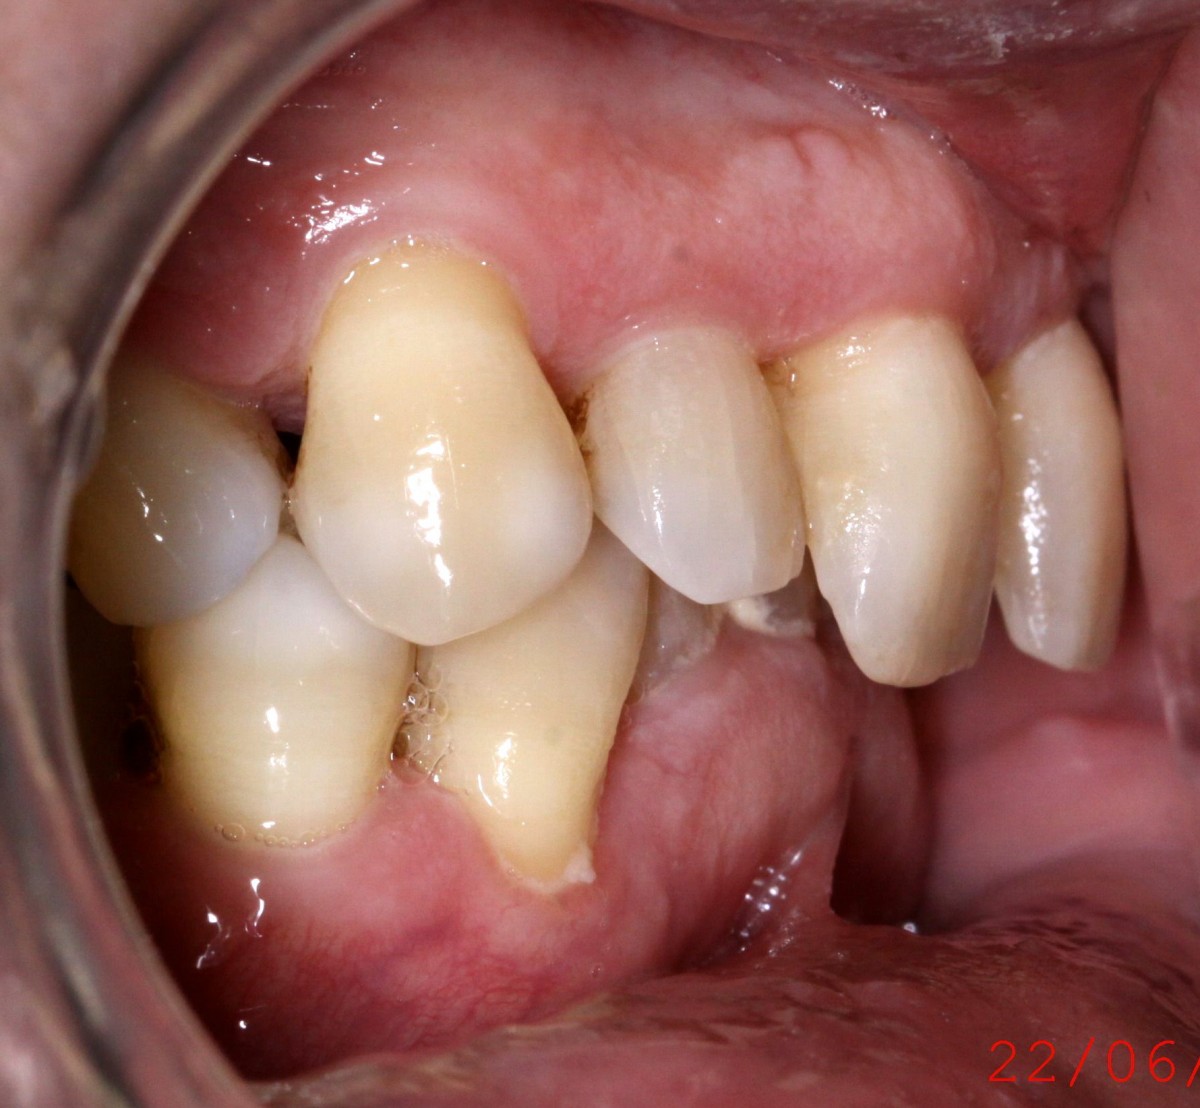

G.L., 51 years old patient, pre- sented to the clinic with Class I malocclusion, deep bite with complete coverage of lower in- cisors, big median diastema between teeth #11 and #21, lack of interdental papilla and poor oral hygiene (figs. 3, 4).

Lower incisors erupted verti- cally and created 2 planes of occlusion and exaggerated curve of spee in the lower arch. The upper lip “pushed” the an- terior incisors lingually and consequently the bite was deepened. Oral hygiene is poor mainly due to the crowding of the lower incisors. The upper diastema resulted in the loss of the interdental papilla between the central incisors (figs. 5, 6).

Patient had gone through pre- vious orthodontic treatment

with extraction of upper first premolars (#14, #24). Space between #11-#21 is slowly opened during the years and space start to develop distally to the upper lateral incisors. Lower incisors are hitting traumatically the palate creat- ing proliferation of the epithe- lium and constant inflamma- tion. Lower anterior crowding is around 4.5 mm (#33-#43) (figs. 7, 8).